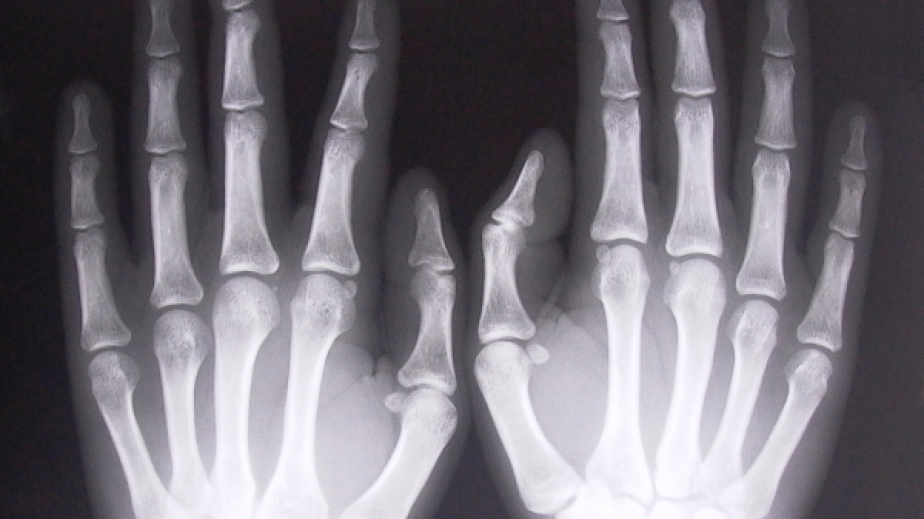

Лек автомобил „Волво”, управляван от 48-годишната Д.К. от Радомир, при движение на заден ход удря мотоциклет „Априлия”, шофиран от неправоспособно 14-годишно момче. Пострадал е непълнолетния, който е с фрактура на китка на ръка, без опасност за живота. Настанен е в „Пирогов” – София за лечение. Двамата водачи не са употребили алкохол.